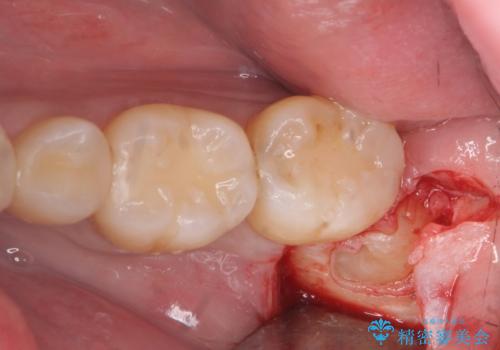

親知らず抜歯

- 親知らずを抜きたいとのことで来院。

パノラマ写真(二次元的な写真)だと、下歯槽神経が近いかどうかわからないので

CT(三次元)を撮り、神経が近くないことを確認して抜歯を行いました。

親知らずがあると手前の歯との隙間に汚れが溜まりやすく、歯ブラシで磨く事はできないため、虫歯になりやすいです。

親知らずは虫歯になれば抜歯をすればいいのですが、手前の歯が虫歯になったら治療が必要になります。

ですので虫歯になる前に抜歯をすることをおすすめします。